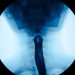

In later stages of esophageal cancer, the tumor may cause symptoms such as difficulty swallowing or pain. Sometimes the tumor is so big that it narrows the esophagus and makes it hard to eat. People with this problem often change their diet, eating smaller and softer foods that will pass more easily through the esophagus. This can lead to weight loss. Swallowing may become painful as the cancer grows, and some people stop eating solid food and switch to a liquid diet.